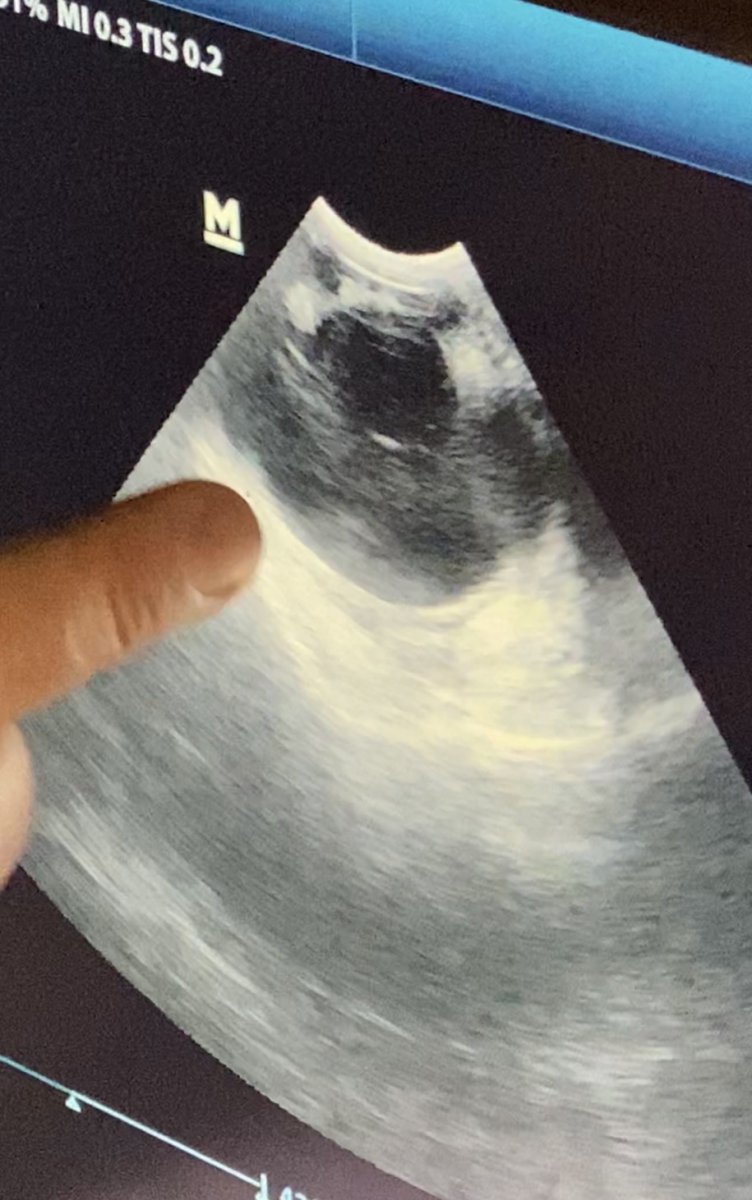

У одной из наших лошадей случился спазм зрачка и воспаление. По каким причинам - хз. У другой был диагноз аутоиммунная неоваскуляризация роговицы. Обе проблемы были замечены вовремя, вылечены, но доктора все равно дождались, сделали диагностику на крутой аппаратуре, узи глаз, получили наиполнейшую консультацию. Что сказать - за эти 3 часа я получила информацию по глазам больше, чем в институте и за всю практику работы с лошадьми. У меня никогда не было проблем с глазами, кроме Аполлона, который в возрасте отьема умудрился дважды наколоть глаз и получить язву роговицы. Мне один раз показали как прижигать и лечить и второй накол я вылечила самостоятельно, и после еще лечила чужим лошадям - 100% успешно и эффективно.

Сейчас обе наши лошади остаются под наблюдением и контролем, с продолжением поддерживающего лечения. А визуально ничего нет?